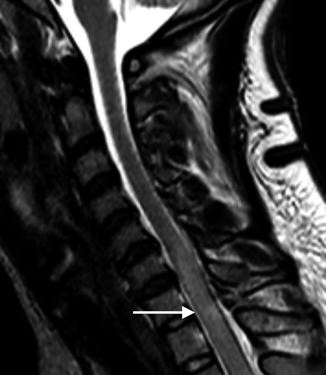

Sagittal CT of the cervical spine displays a mild distracted fracture of the C7 spinous process (arrow) without malalignment in a 35-year-old patient following a motor vehicle accident. Of note, the intracanalicular contents include the spinal cord that cannot be reliably assessed on this image

Sagittal T2-weighted MR image reveals abnormal cord signal indicative of cord contusion/edema (arrow) that was not apparent by CT